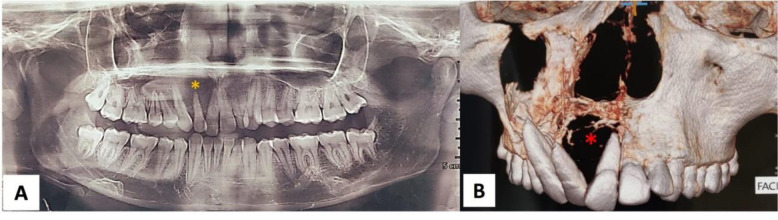

摘要头颈部尤因肉瘤(ES)是一种罕见的肿瘤。ES最常见的部位是长骨,占58%,头颈部仅占3%。在这里,我们强调了一个独特的表现,ES累及上颌区域在一个21岁的男性。患者出现右上颌骨肿胀2个月。影像学检查显示溶骨病变累及右上颌骨。尤因氏肉瘤很少影响头颈部,由于它模仿了许多常见的病变,因此给诊断带来了挑战。准确的诊断需要多学科的方法,包括临床、放射学、组织病理学和分子评估。

Ewing sarcoma (ES) of the head and Neck is a rare entity. The most common location for ES is long bones accounting for 58%, with head and neck accounting only for 3% of all the sites. Here we highlight a unique presentation of ES involving the maxillary region in a 21-year-old male. Patient presented with right maxillary swelling for the last 2 months. Imaging studies reveal osteolytic lesion involving the right maxilla. Ewing's sarcoma rarely affects the head and neck region, posing diagnostic challenges as it mimics many common lesions. Accurate diagnosis requires a multidisciplinary approach involving clinical, radiological, histopathological, and molecular evaluations.